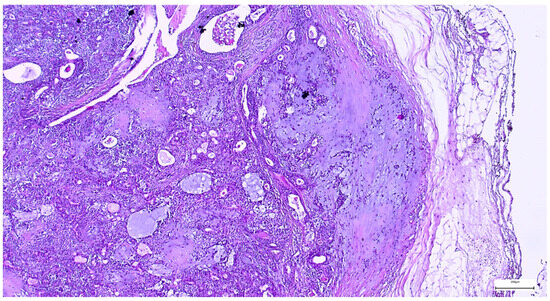

On gross examination, most pleomorphic adenomas appeared as well-demarcated, bosselated, gray-white myxoid masses. Intraoperative salivary imprint cytology was applied if tumors contained areas of necrosis, hemorrhages, or infiltrative margins. Tumor sizes ranged from 9 to 82 mm, with a mean diameter of 32.55 ± 13.38 mm. Histological examination of pleomorphic adenomas revealed the characteristic biphasic epithelial–myoepithelial architecture. The tumors displayed a heterogeneous cellular composition (248 cases; 98.02%), while the pleomorphic adenoma oncocytic subtype was identified in five cases (1.98%) (Table 3). The stromal component exhibited marked variability, the myxoid phenotype being the predominant pattern (138 cases; 54.54%), followed by chondromyxoid phenotype (72 cases; 28.45%) (Figure 4 and Table 3).

Figure 4. Multinodular, biphasic tumor cells proliferation, embedded in a chondromyxoid stroma and surrounded by a thin hypocellular fibrous capsule in pleomorphic adenoma (H&E staining, 5×).